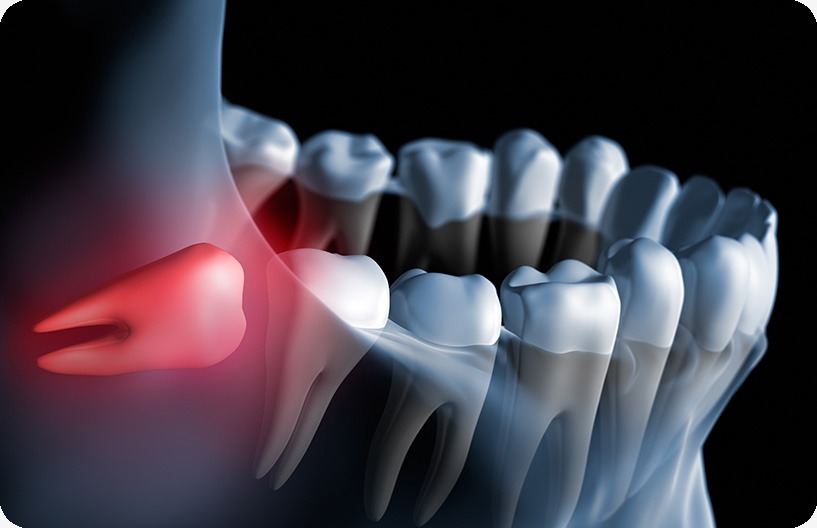

Oftentimes there is not enough room to accommodate wisdom teeth, which can impede their ability to grow into the mouth correctly. For some people, the wisdom teeth only partially emerge through the gums, which can result in cavities, crowding issues with the surrounding teeth, gum infections, and/or severe pain. When they are first developing, the wisdom teeth may begin to grow in an unusual direction. This uneven development may be responsible for several problems, including crowding and damage to the adjacent second molars. When there is not enough space for the wisdom teeth to erupt into your mouth at all, this is known as ‘Impacted Wisdom Teeth.’ When wisdom teeth are impacted in the jaw, the opening around the teeth may become a fertile ground for bacteria to start developing, leading to infection in the gum tissues causing severe discomfort, swelling, pain, and illness. Early removal of impacted wisdom teeth is often recommended to avoid future problems and to avoid costly surgical procedures.

Through the use of digital x-rays and a full and complete oral exam, Donsdale Dental will be able to perform a thorough examination of your teeth and gums to determine exactly what is going on in your gums and bone tissue and decide if an extraction is required.